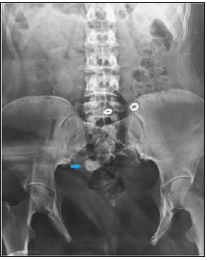

A 21-year-old woman with history of bladder extrophy, for which she had undergone an enterocystoplasty with bladder enlargement and mitrofanoff type bypass; She is under intermittent catheterization since the age of 6, and a vaginal reconstruction with labioplasty is planned for her; the patient presented with a one-year history of recurrent urinary tract infections, difficult self-catherization and a pelvic heaviness. The operative details of all her surgeries were not available to us. A pelvic MRI was performed, as part of surveillance, revealing a large neo-bladder calculi measuring 27x15mm (Figures 1-3), ultrasound has shown no renal lithiasis or hydronephrosis and the creatinine clearance was normal (49μmol/l), the calculi was radio-opaque on X-ray abdomen (Figure 1). Physical examination of her abdominopelvic region revealed multiple scars, a catheterizable stoma, and an ablated urethra (Figure 2).

Figure 1: Abdomen Xray showing a radio-opaque calculi.

Figure 3:MRI showing a large bladder calculi (27x15mm).